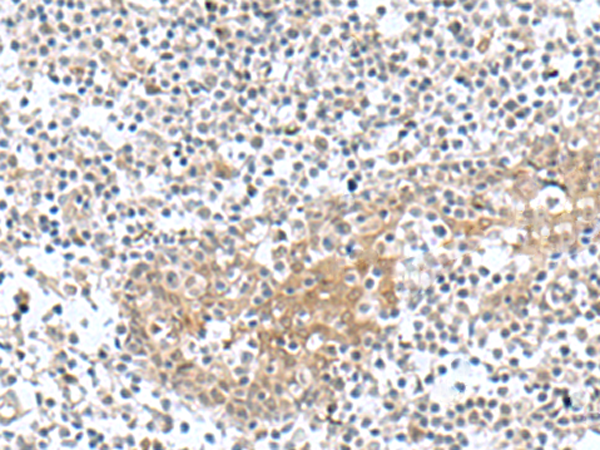

ELISA, WB, IHC |

IHC positive control: |

Human tonsil |

IHC Recommend dilution: |

50-100 |